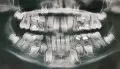

Такое прорезывание бывает, промежуток между временными зубами - это вариант нормы.

Пятно на зубе - гипоплазия эмали. Выше риск развития кариеса.

К детскому стоматологу обратиться можно в любом возрасте.